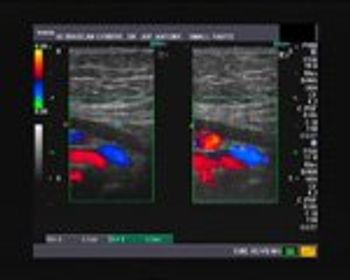

This is a 30 year old female with polymenorrhea with dysmenorrhoea. What do the ultrasound images show?